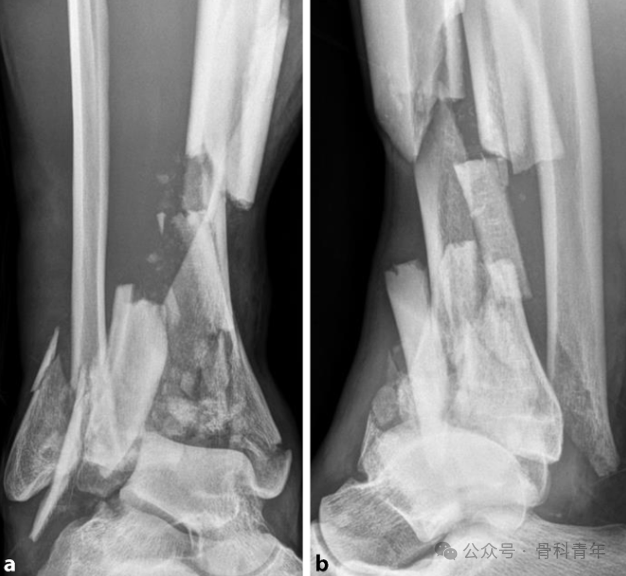

腓骨完整时,胫骨承受轴向压力而发生的骨折(a); -